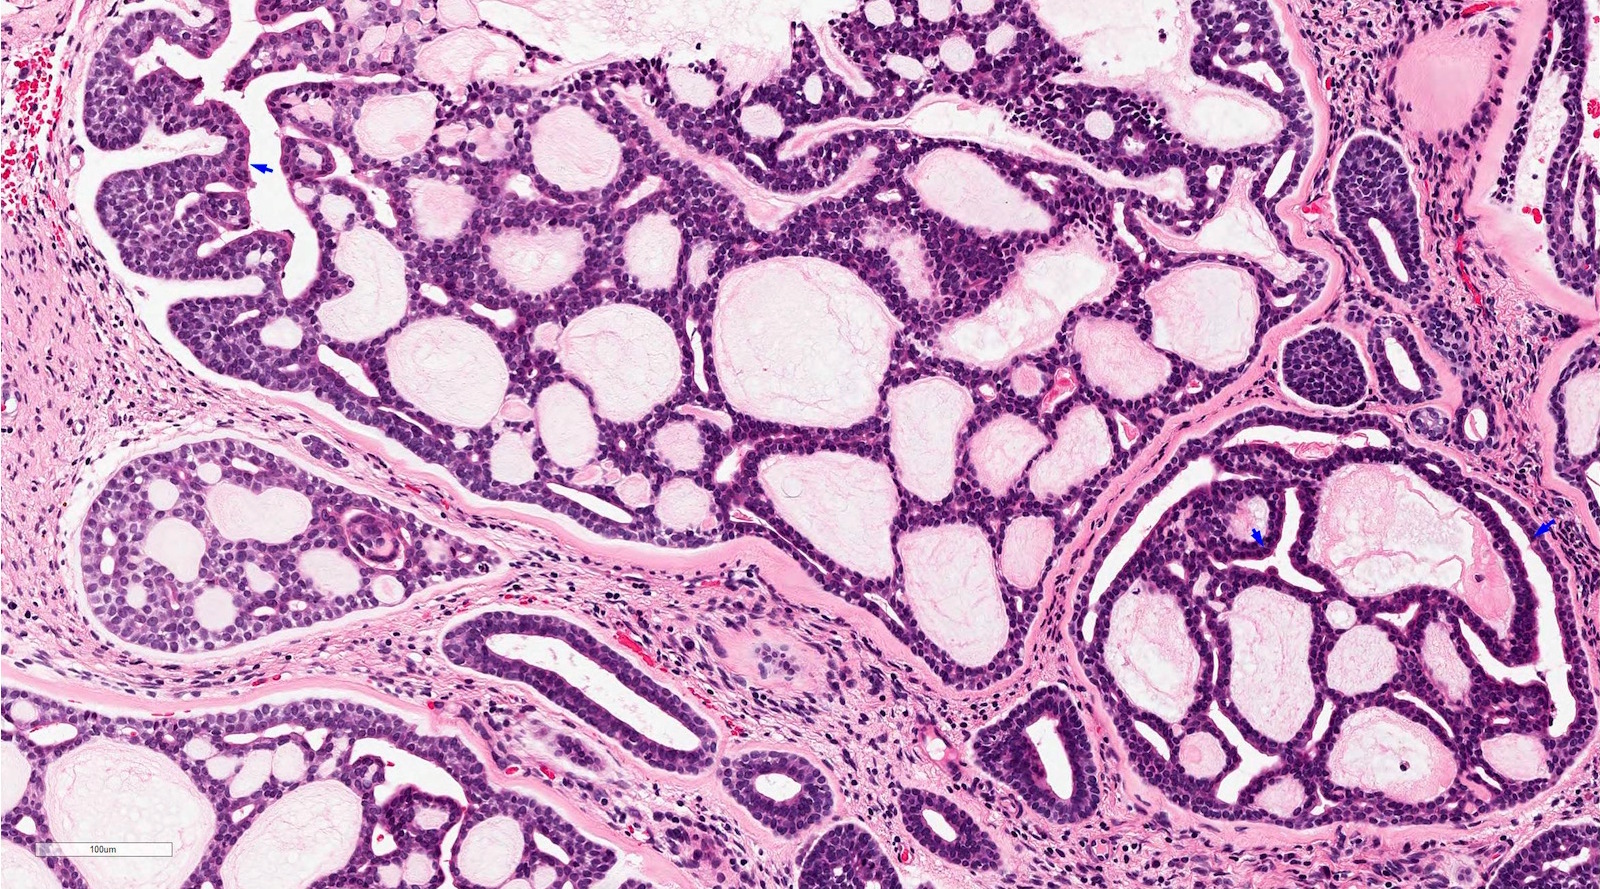

Mucoepidermoid Carcinoma (MEC) & Warthin-like MEC

Mucoepidermoid Carcinoma (MEC) including Warthin-like MEC